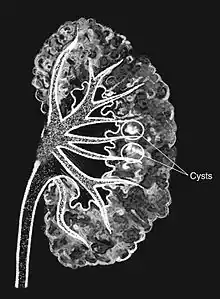

| Medullary sponge as seen on an intravenous pyelogram | |

Classically, MSK is seen as hyperechoic papillae with clusters of small stones on ultrasound examination of the kidney or with an abdominal x-ray. The irregular (ectatic) collecting ducts are often seen in MSK, which are sometimes described as having a "paintbrush-like" appearance, are best seen on intravenous urography. However, IV urography has been largely replaced by contrast-enhanced, high-resolution helical CT with digital reconstruction.[8]